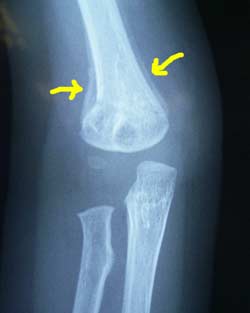

8月3日 うっすらと新しい骨が見える。一時的に骨が太くなるが、成長と共に他の部分とかわらなくなるそう。 あと一週間でギプス卒業である。 |